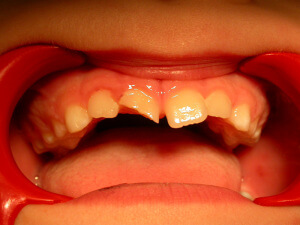

Interceptive Orthodontics

There are ways to prevent orthodontic problems and avoid braces. It’s essential to check our children early and on a regular basis, to avoid teeth crowding, discontinue a bad oral habit, or in order to guide favorably the facial and dentoalveolar development.